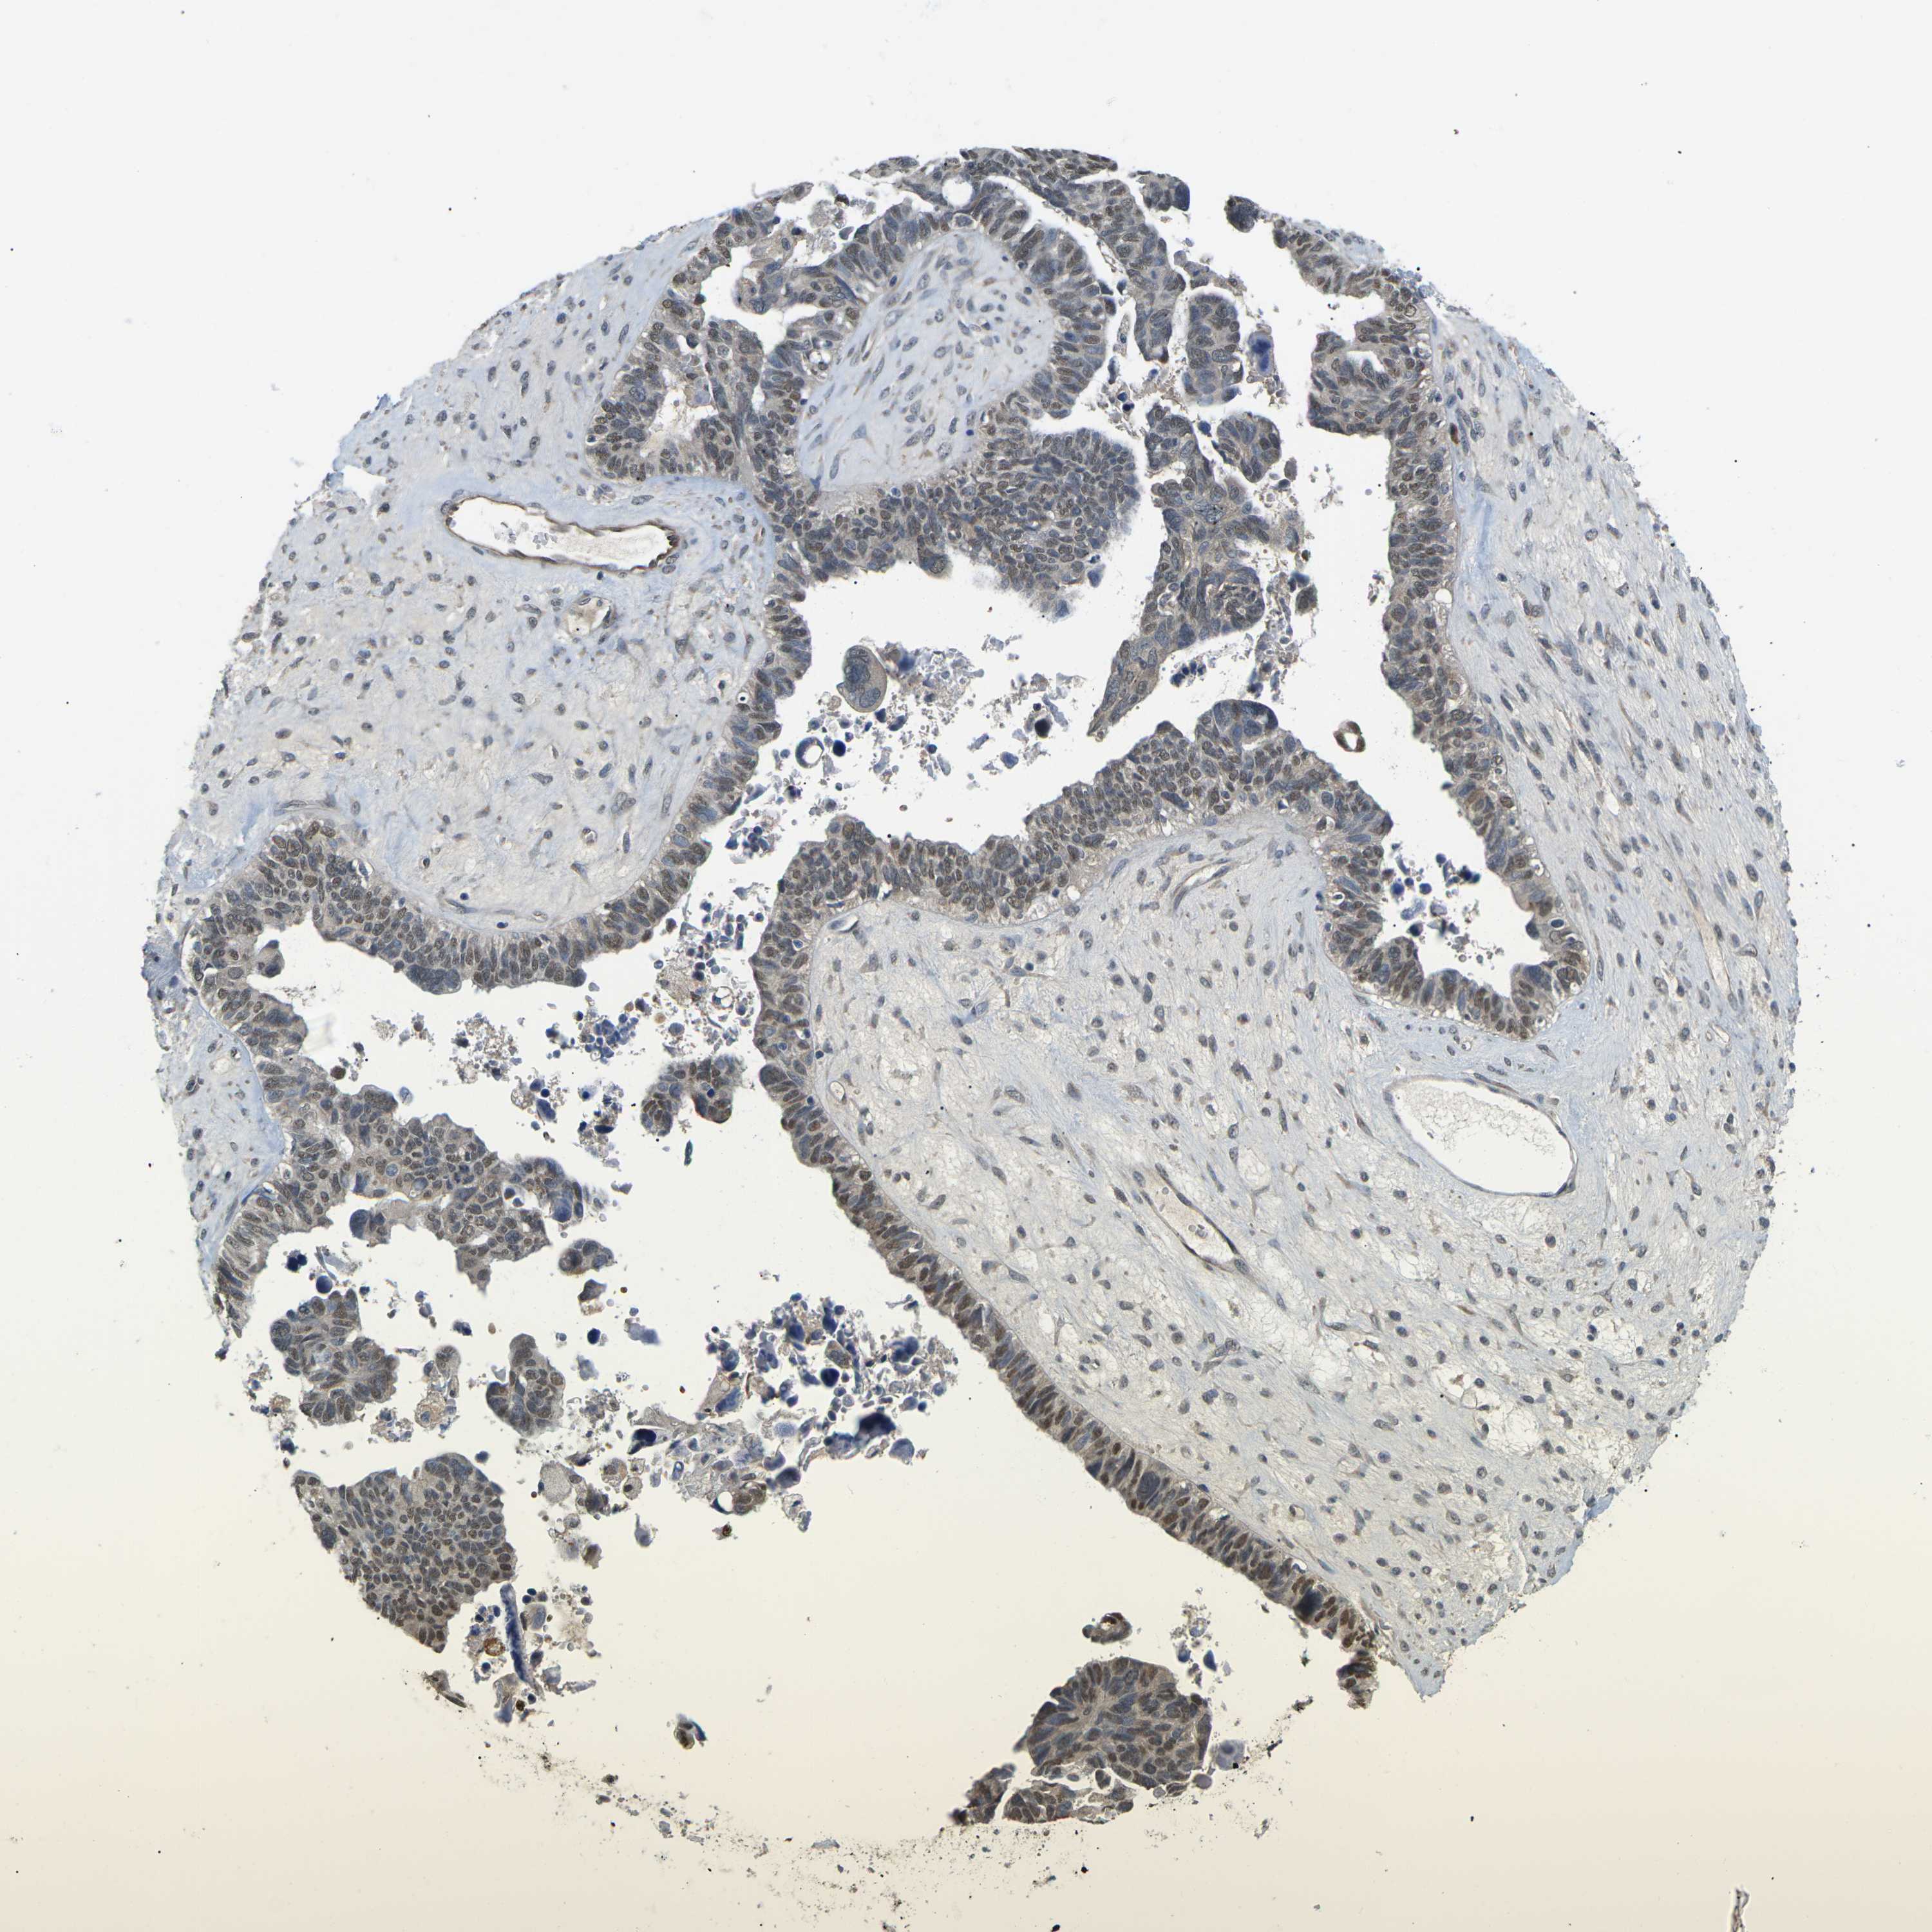

OVARIAN CANCER - Protein expressioni

A mouse-over function shows sample information and annotation data. Click on an image to view it in a full screen mode. Samples can be filtered based on level of antibody staining by selecting one or several of the following categories: high, medium, low and not detected. The assay and annotation is described here.

Antibody stainingi

Antibody staining in the annotated cell types in the current human tissue is reported as not detected, low, medium, or high, based on conventional immunohistochemistry profiling in selected tissues. This score is based on the combination of the staining intensity and fraction of stained cells.

Each image is clickable and will lead to virtual microscopy that enables deeper exploration of all samples and also displays staining intensity scores, fraction scores and subcellular localization as well as patient and tissue information for each sample.

Antibody HPA012016

Antibody CAB000276

Antibody CAB025522

Cystadenocarcinoma, serous, NOS

Carcinoma, endometroid

Cystadenocarcinoma, mucinous, NOS

Carcinoma, NOS